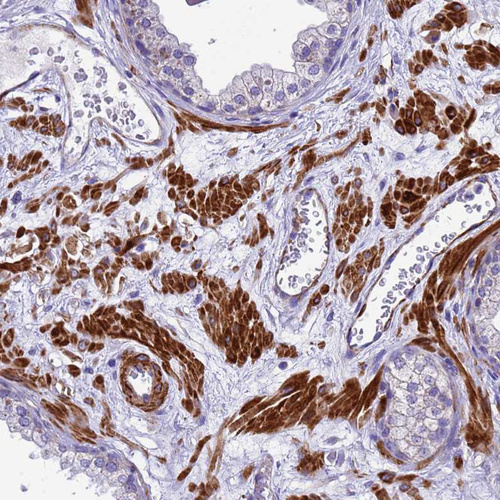

Immunohistochemical staining of human cerebral cortex shows moderate cytoplasmic positivity in neurons.